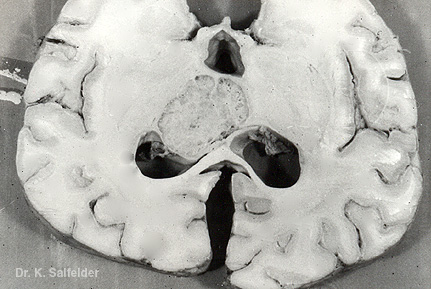

Abb. 12,8: Kryptokokkose

Auf dieser sagittalen Schnittflaeche des Gehirns ist ein grosser grau-weisser Herd (Kryptokokkom) zu erkennen